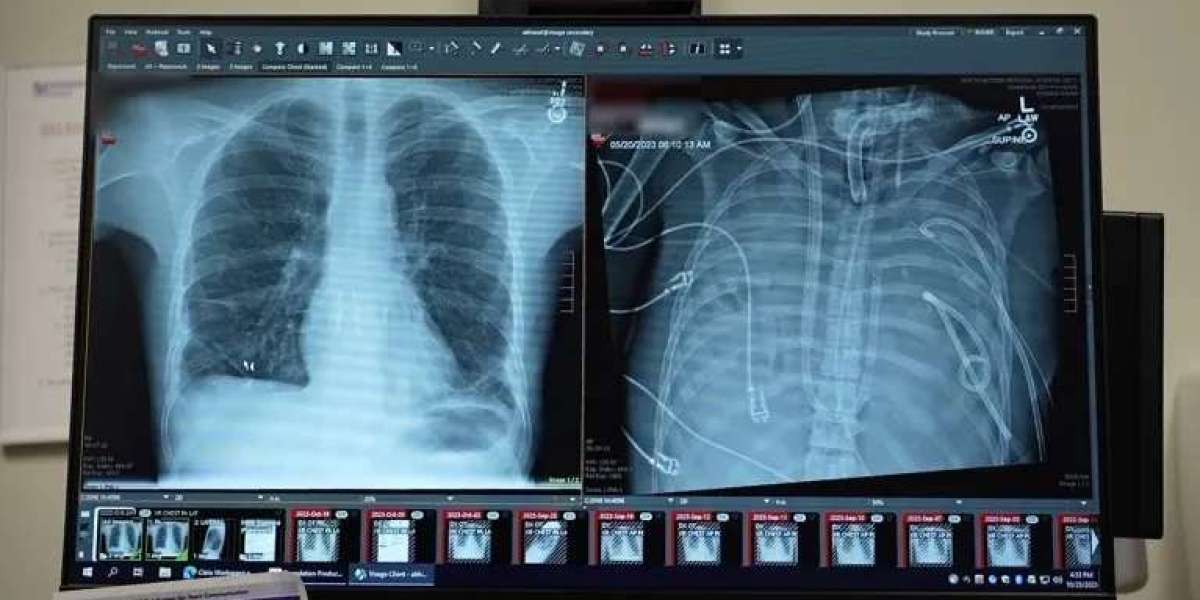

X-rays show a 33-year old patients’ new lungs (left) and old lungs (right) | Northwestern Medicine

The patient, a 33-year-old man, developed acute respiratory distress syndrome (ARDS) triggered by influenza B, complicated by a severe drug-resistant Pseudomonas infection. Conventional ventilators could not sustain his failing lungs, which were filled with pus, leading to sepsis, kidney failure, and cardiac arrest.

After 48 hours, a suitable donor became available, allowing for a successful double lung transplant. Two years later, the patient continues to enjoy normal lung function with no signs of organ rejection, showcasing the TAL system’s effectiveness and the surgical team's precision.